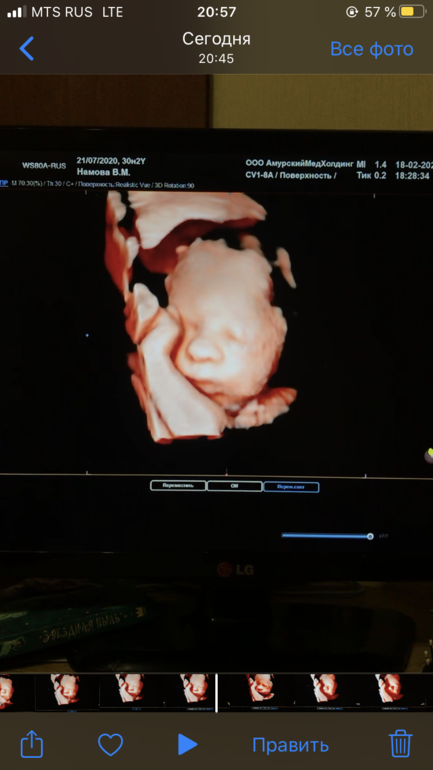

30+2 3 скрининг пройден. И фоточка человечка

Ну и фотка карапуза в 3D,вот смотришь вроде все одинаковые,а потом находишь черты себя и мужа 😅

Классный малыш, уже совсем человечки со своими чертами лица.

У вас такое фото хорошее получилось, у нас закрылся ручками только щеки было видно)

У нас тоже закрывался

Руку себе на лоб положил и так и лежал

Вторую сторону лица так полноценно и не рассмотрели 😅